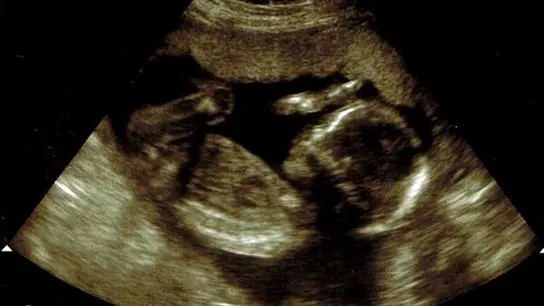

laSexta se ha remitido a la Ley de Salud que se aprobó en Nueva York y en esa ley no se permite matar a un bebé después de nacer. Lo que sí dice esa ley aprobada en enero es que se podrá abortar en el tercer trimestre, en la recta final del embarazo.